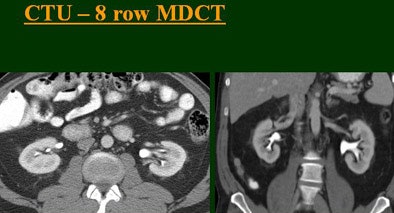

"As we've been scanning through the kidneys, we've been noticing that there has been an increase in the quality images as we go from (single-) to four-, eight-, and 16-row detector scans," Raptopoulos said. "Our purpose, then, was to assess the quality of CTU with progressively improving CT technology from (single-) to 4-, 8-, and 16-row scanners, using a split-injection single scanning technique."

| Top to bottom: Split-bolus CTU improves significantly using a nearly identical protocol but with the addition of more detector rows, from single- (spiral), four-, eight-, and 16-row scanners. All images courtesy of Dr. Vassilios Raptopoulos. |

The single-row scanner required two breath-holds; the other scanners reduced scan time from about 20 seconds (four-slice) down to seven seconds (16-slice). Collimation for the single-row scanner was 5 mm, with 3-mm overlapping reconstructions. Collimation for the four-, eight-, and 16-row scanners was 2.5 mm, 1.5 mm, and 0.5 mm, respectively, with the patients scanned in a prone position.

Based on multiplanar reformatted (MPR) images, there was significant upscale improvement in calyceal detail from the isotropic images provided by single-detector scanning (median score 2) to four- (median score 3), eight- (median score 4), and 16-detector scanning, Raptopoulos said. On MPR images the calyceal were 1, 2, 3, and 5, respectively. The median ureteral filling was 4 for the upper and left-lower ureters, and 3 for the right-lower ureters.